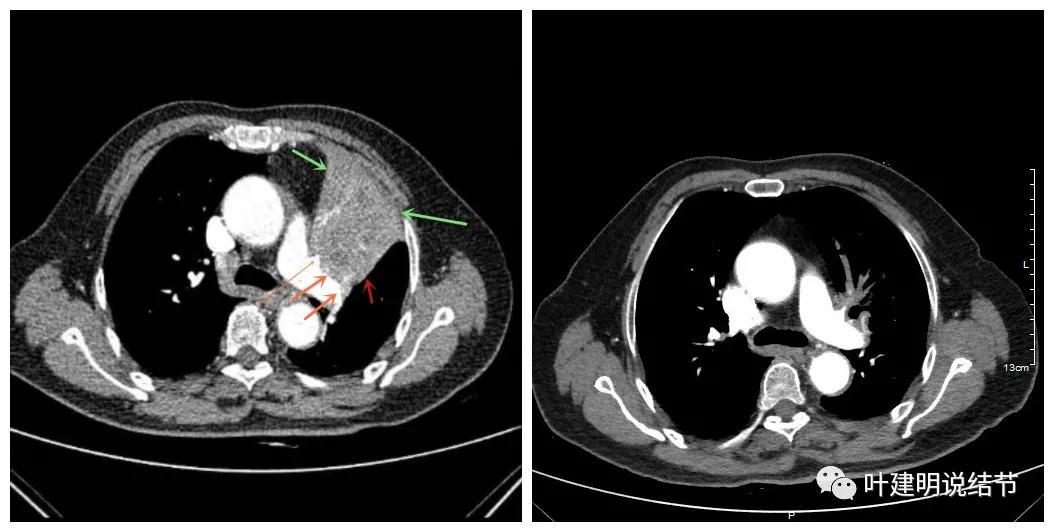

上图绿色示左上叶支气管,蓝色示下叶支气管开口处

上图示汇总区

上图示原病灶处,现在不是明显的占位影像了

可见效果相当的好,如果我们把差不多同样层面的放到一起对比,更能显示化疗加免疫的惊人效果: